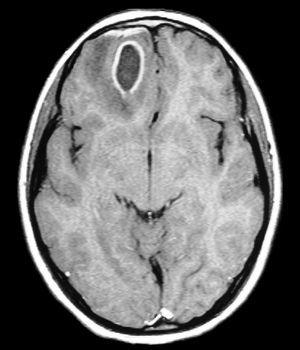

Niña de 8 años con cefalea frontal de 10 días y vómitos y decaimiento en los últimos 2 días. En otro hospital se realiza TC craneal que muestra tumoración frontal derecha con edema y efecto masa, con desplazamiento de línea media y compresión parcial del sistema ventricular izquierdo (fig. 1). Se traslada a nuestro hospital presentando a las 3 h del ingreso disminución de conciencia con hipertonía generalizada en opistótonos, cianosis acra y perioral. Como antecedentes presenta una comunicación interventricular membranosa con hipertensión pulmonar suprasistémica e insuficiencia tricuspídea leve en tratamiento con ácido acetilsalicílico, dipiridamol y captopril. A la exploración destaca una subcianosis perioral, soplo sistólico II/VI, midriasis izquierda, aftas orales con piezas dentarias cariadas y un hígado a 3 cm de reborde costal. Presenta una analítica con 13.600 leucocitos/μl (85 % granulocitos) y proteína C reactiva (PCR) 1,26 mg/dl. Se instaura tratamiento con dexametasona y valproato. Se realiza craneotomía y drenaje, extrayéndose material purulento en la región frontal derecha. Es tratado con cefotaxima y metronidazol durante 3 semanas y posteriormente 2 semanas más con amoxicilina-ácido clavulánico. También posteriormente se procede a la extracción de las piezas dentarias cariadas. Como secuelas presenta crisis comiciales secundarias a cicatriz cortical.

Figura 1.TC craneal: absceso frontal derecho con gran desplazamiento de línea media. Caso 4.